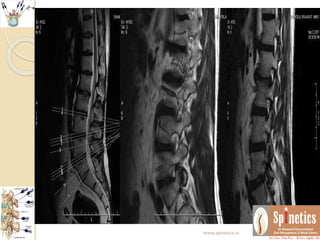

Unusual case

 A male 42 years had acute excruciating leg and back pain

 Subjected to pain management after lots of consents

 Within 24 hours, Injected transforaminal ozone after

confirmation with non ionic contrast

 Waited for few minutes till any untowards events to

occur

 With comfortable vital parameters, planning to shift him

in recovery area, rather he immidiately walk out pain free

 Even long term followup kept to see any reoccurance

 Neurological behaviour differs in same presenting

spine conditions

 Even though we repeated MRI in one month span as

there is no reccurance what it suggest

 There is resolving annular tear with sequestration

 Many of our patients we routinely found such

herniations which might be too painful to the

patients

 In opposite this patient was not having any

symptoms regarding reccurance of pain

 This the follow-up of more than 2and half years